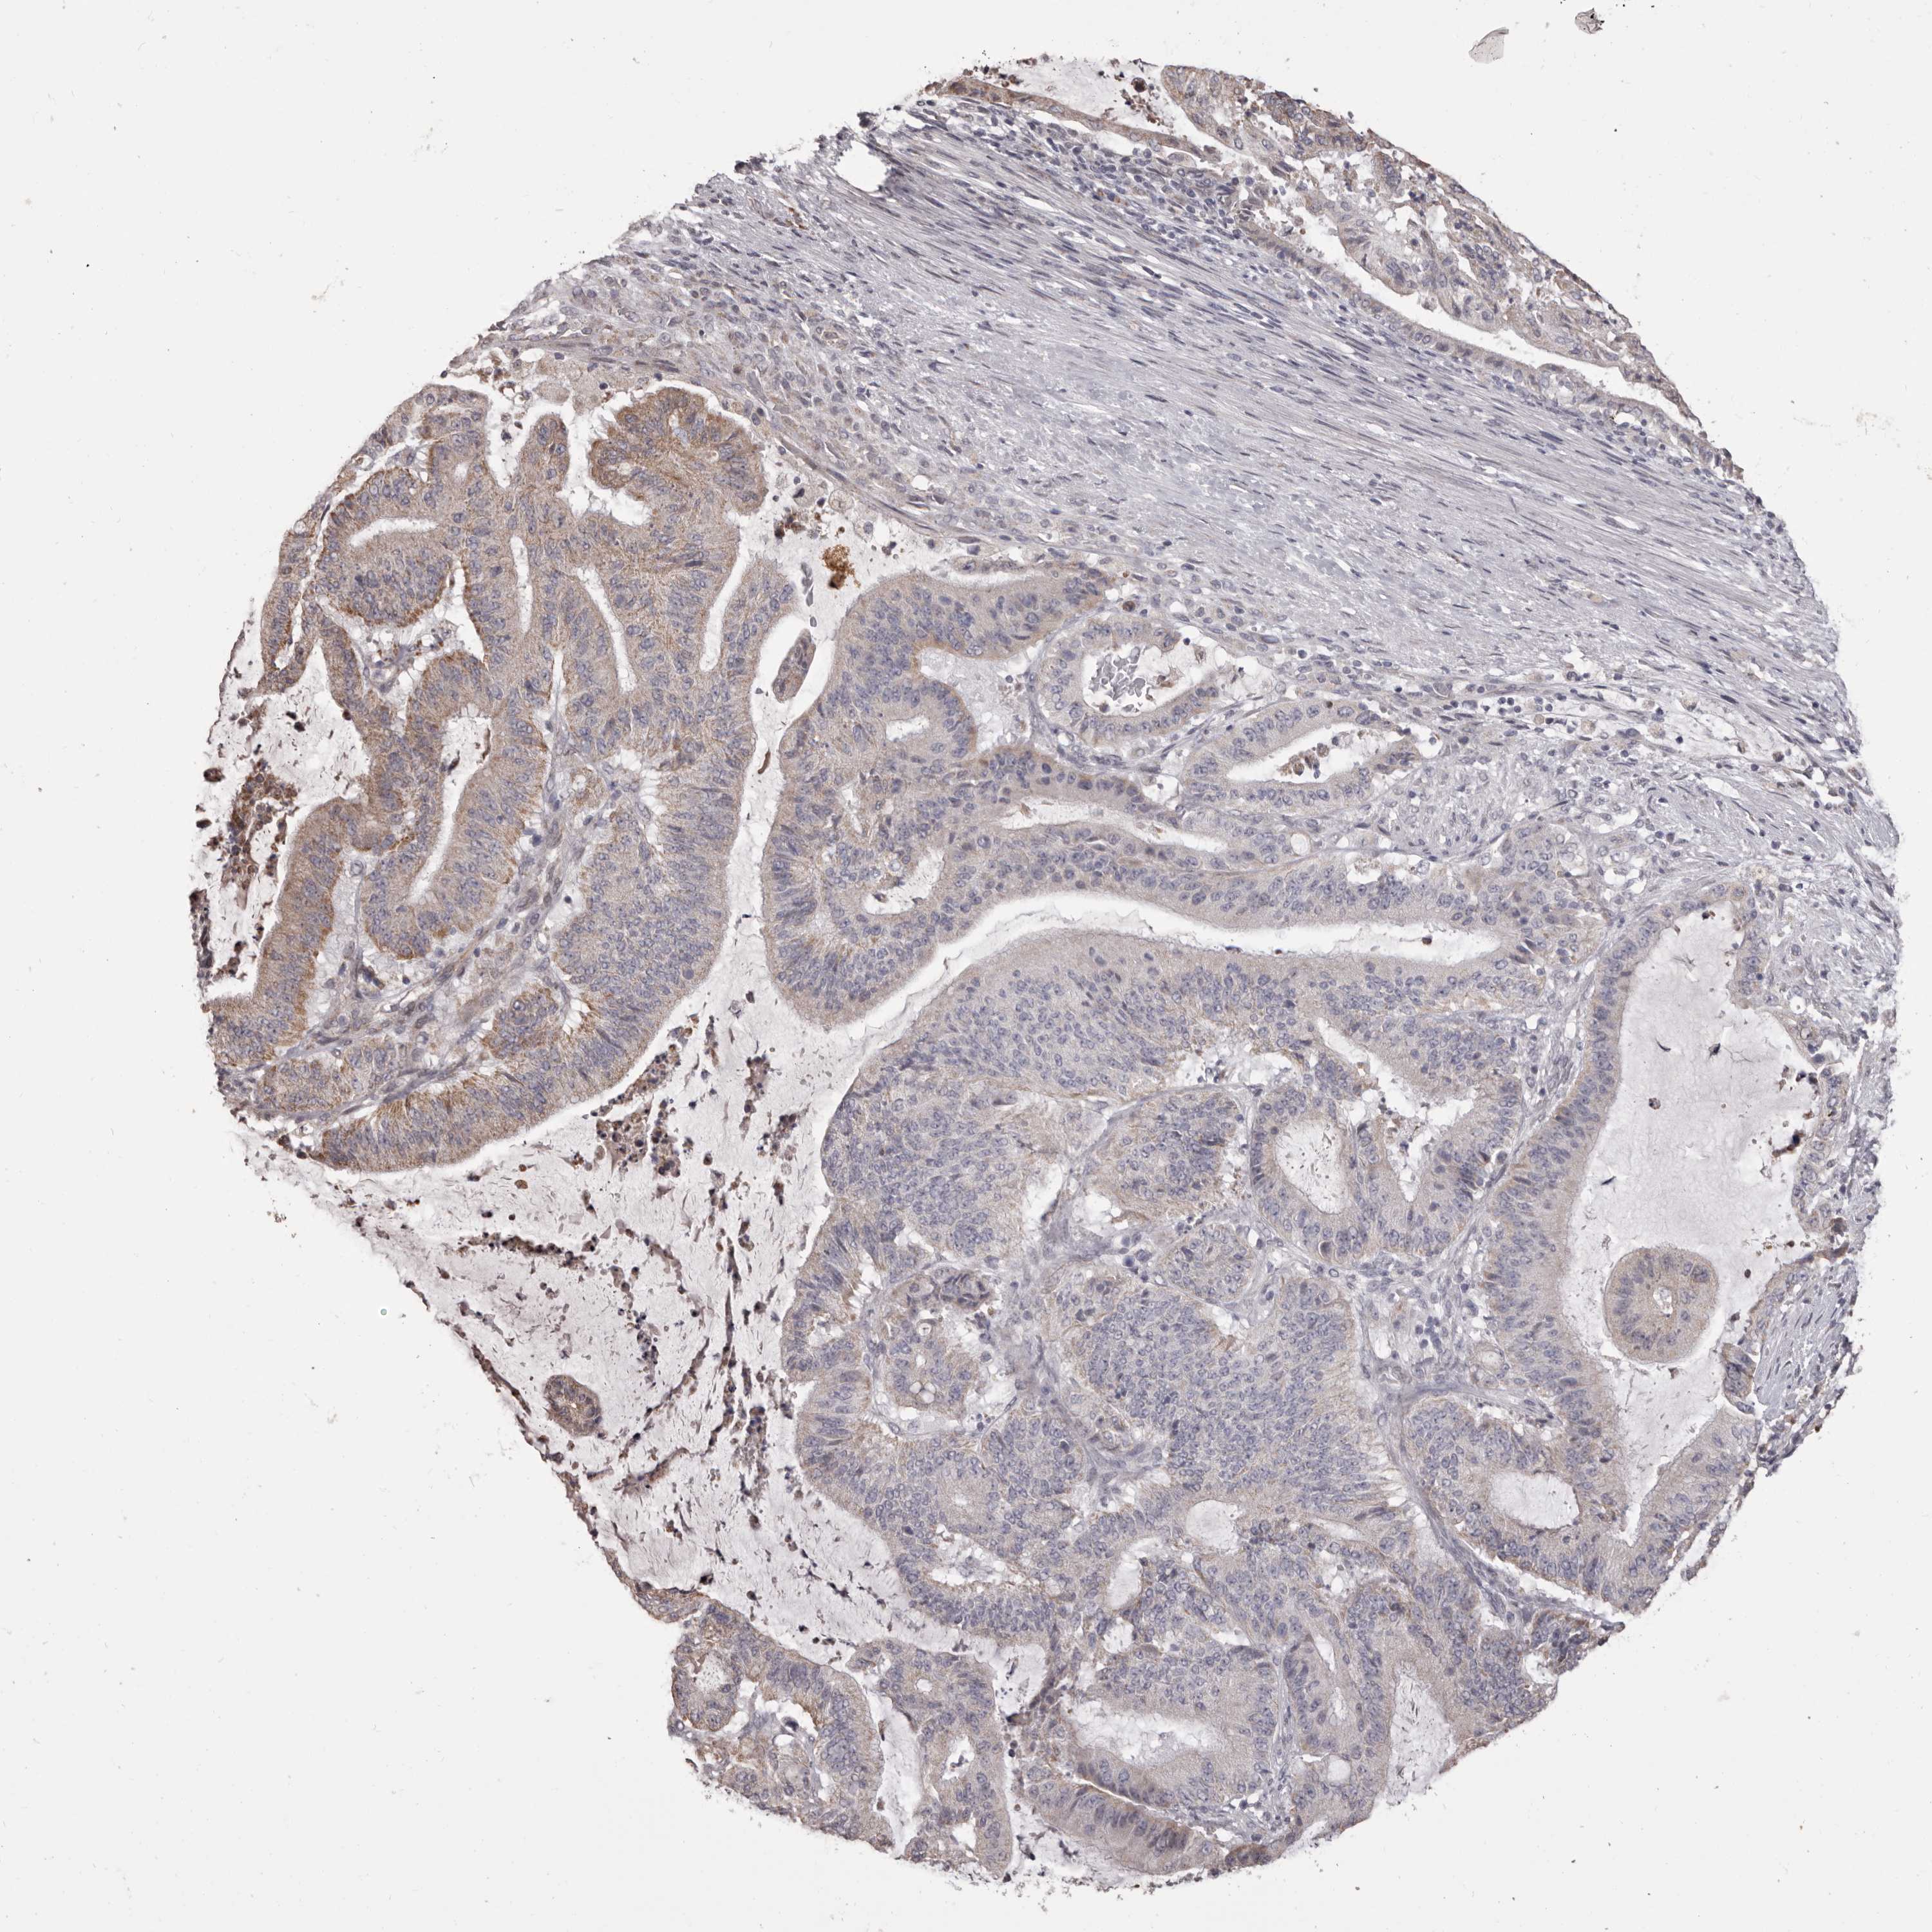

LIVER CANCER - Protein expressioni

A mouse-over function shows sample information and annotation data. Click on an image to view it in a full screen mode. Samples can be filtered based on level of antibody staining by selecting one or several of the following categories: high, medium, low and not detected. The assay and annotation is described here.

Note that samples used for immunohistochemistry by the Human Protein Atlas do not correspond to samples in the TCGA dataset.

Antibody stainingi

Antibody staining in the annotated cell types in the current human tissue is reported as not detected, low, medium, or high, based on conventional immunohistochemistry profiling in selected tissues. This score is based on the combination of the staining intensity and fraction of stained cells.

Each image is clickable and will lead to virtual microscopy that enables deeper exploration of all samples and also displays staining intensity scores, fraction scores and subcellular localization as well as patient and tissue information for each sample.

Antibody HPA029795

Antibody CAB022338

Staining

High

Medium

Low

Not detected

Intensity

Strong

Moderate

Weak

Negative

Quantity

>75%

75%-25%

<25%

None

Location

Nuclear

Cytoplasmic/membranous

Cytoplasmic/membranous,nuclear

Cholangiocarcinoma

Carcinoma, Hepatocellular, NOS